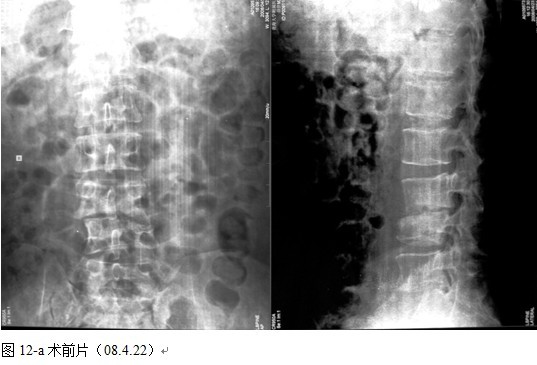

本组46例中男28 例,女18 例。年龄17~67岁,病程6 个月~7年,平均11.3 个月。本组患者均为 L1~S1腰段结核。病灶累及2 个椎体31例(L1-2 6例, L2-3 8例,L3-4 10例,L4-5 5例,L5-S1 2例),3 个或3 个以上椎体15例。合并腰大肌脓肿23列,所有患者均有腰背部疼痛,活动受限,双下肢感觉麻木19例,会阴部感觉减退12例,双下肢肌力减弱12例,腱反射减弱12例,术前后凸角(Cobb 角) <30°者12例, 30°~60°者28 例, >60°者6 例,Cobb角平均32.3°4例患者是二次手术。术前均行X线片、CT或者MRI检查。术后病理检查确诊为脊柱结核。

本组手术用时间3~4h , 平均3.5h 。术中出血300~500ml , 平均约350ml 。术后症状完全缓解,无神经功能障碍加重等并发症,1例营养差的老年患者伤口出现窦道,1例因肝功能差,术后未口服抗痨药,伤口出现窦道,经换药后二期愈合,其余病例伤口均一期愈合。马尾神经受损的患者术后基本恢复正常。术后一周后凸角平均 5.4°后凸畸形平均矫正90%以上, 最终后凸角平均8.3°,后凸角度平均丢失4.2°。随访3个月有87%(40/46)有骨痂形成,6个月91.3%(42/46)明显骨性愈合(见图),其余4例9-12个月内愈合,随访时间3-32个月,平均11个月,46例患者中2例在术后2个月和3个月时背部形成脓肿,换药后治愈。2例出院1月后并发结核性脑膜炎,治疗后好转。1例因椎弓根钉偏外,刺激神经根,5个月后从侧方脱出,疼痛加重,因前后路植骨完全愈合,取出后症状完全缓解。